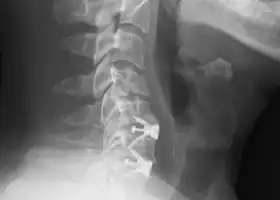

![]() X-rays of anterior cervical discectomy and fusion, C5C6 and C6C7. Lateral view. | |

Anterior cervical discectomy and fusion (ACDF) is a surgical procedure to treat nerve root or spinal cord compression by decompressing the spinal cord and nerve roots of the cervical spine with a discectomy, followed by inter-vertebral fusion to stabilize the corresponding vertebrae.[1] This procedure is used when other non-surgical treatments have failed.

The neurosurgeon or orthopedic surgeon enters the space between two discs through a small incision in front (= anterior) of and at the right or left side of the neck. The disc is completely removed, as well as arthritic bone spurs. The disc material, pressing on the spinal nerve or spinal cord, is then completely removed. The intervertebral foramen, the bone channel through which the spinal nerve runs, is then enlarged with a drill giving the nerve more room to exit the spinal canal.

To prevent the vertebrae from collapsing and to increase stability, the open space is often filled with a graft. That can be a bone graft, taken from the pelvis or cadaveric bone; or an artificial implant.[4] The slow process of the bone graft joining the vertebrae together is called "fusion". Sometimes a titanium plate is screwed on the vertebrae or screws are used between the vertebrae to increase stability during fusion, especially when there is more than one disc involved.